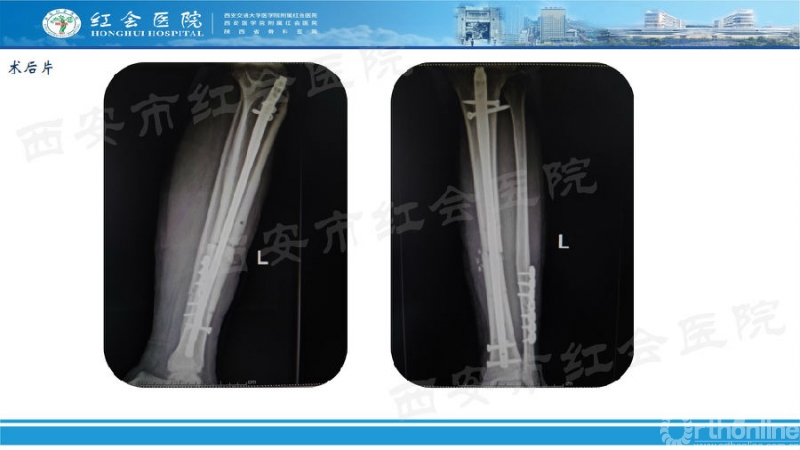

经典病例展示

(图片滑动展示)